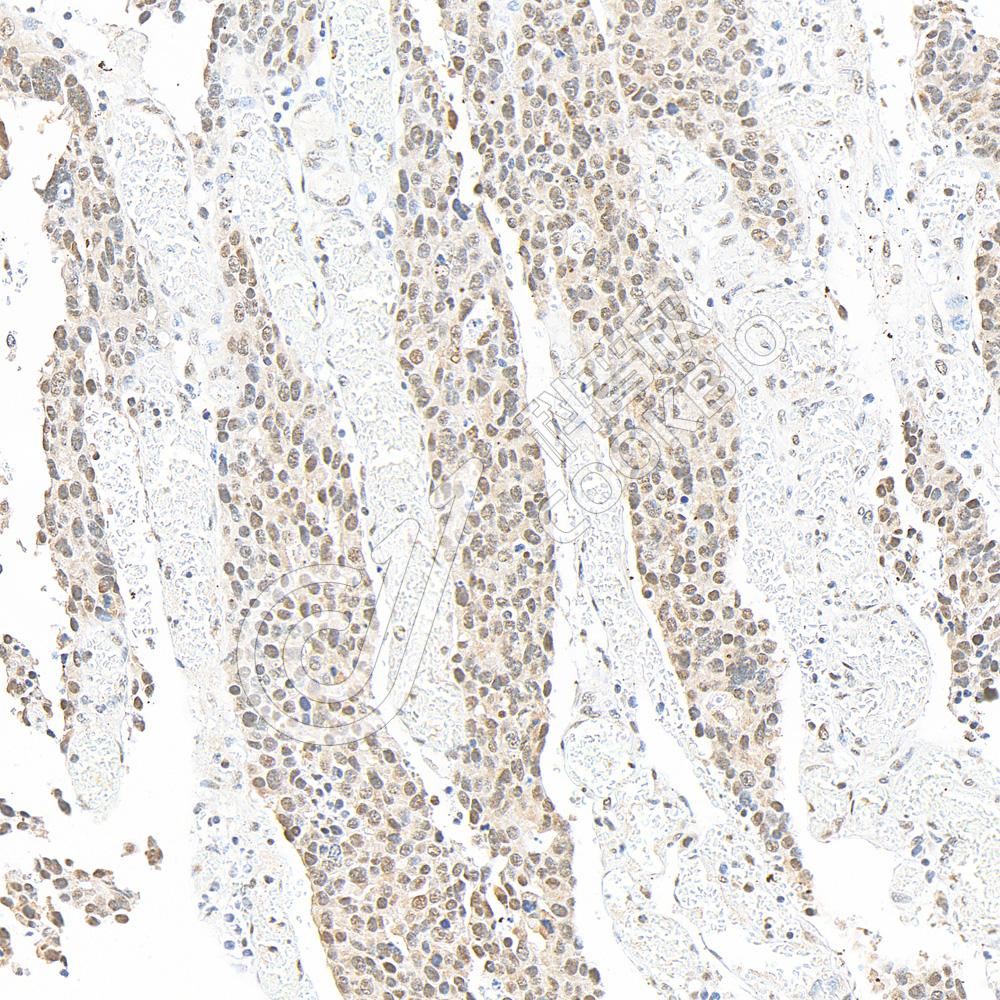

Anti-p38 兔多克隆抗体

兔多抗

MAPK通路

IHC/IF

H,M,R

货号:K133015-100

规格:100 μL

¥ 1900

M

货号:K1333174-100